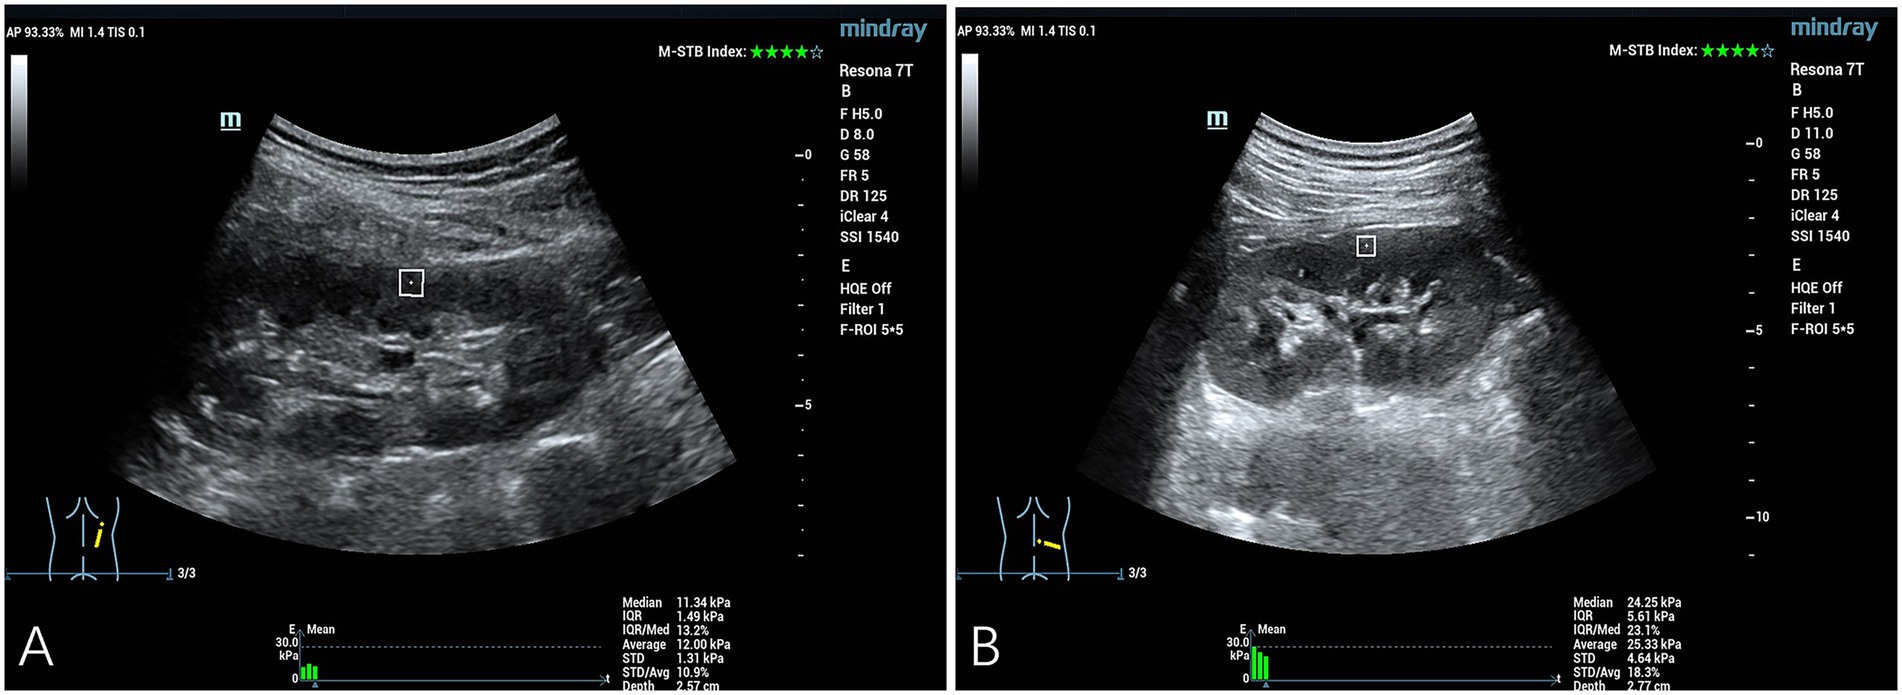

Comparison of YM values in the right renal cortex between the control group and the simple hypertension group: The YM value in the right renal cortex of the simple hypertension group was higher than that of the control group, and the difference was statistically significant (p < 0.05) (Table 2 and Figure 1).

Figure 1. Quantitative assessment of SWE in the right renal cortex. (A) The YM measurement obtained from the right renal cortex of a representative healthy control subject was 11.34 kPa. (B) The YM measurement obtained from the right renal cortical tissue of a patient diagnosed with hypertension demonstrated an elevated value of 24.25 kPa.